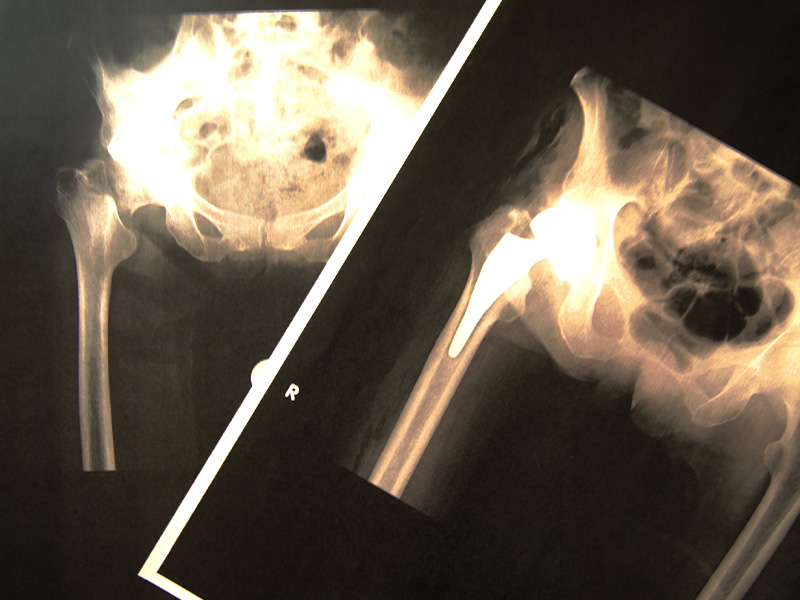

主な治療内容について【整形外科・リハビリテーション科・リウマチ科】

当院では、関節疾患・脊椎疾患・外傷治療を中心に、幅広い症状に対応しております。膝や腰の痛み、交通事故後の治療、労災に関するご相談など、お気軽にお問い合わせください。患者様の快適な生活をサポートいたします。

関節疾患、リウマチ

外傷、交通事故、労災

骨疾患